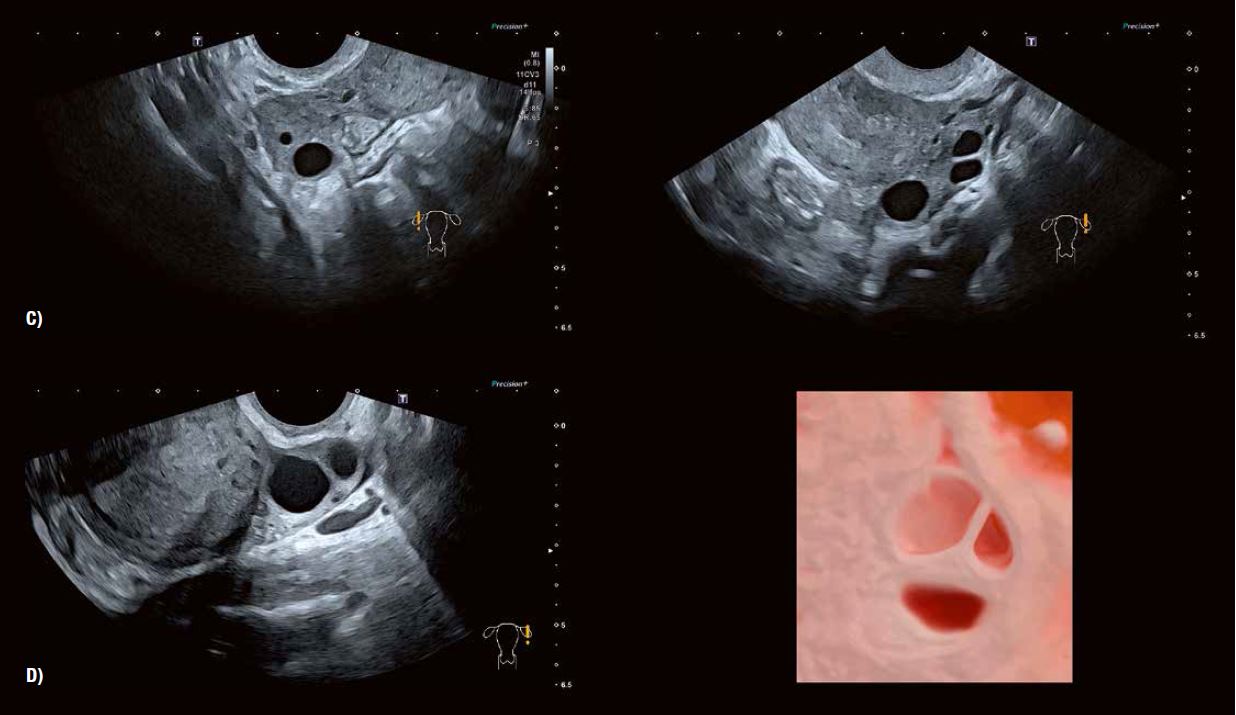

Ультразвукове дослідження та моніторинг росту фолікулів під час природного або пов'язаного з допоміжними репродуктивними технологіями циклу вже давно стали загальноприйнятою практикою. Прогрес у технології УЗД значно підвищив можливості оцінки дозрівання фолікулів та прогнозування початку овуляції (рис. 5). Сканування у високій роздільній здатності в сірій шкалі демонструє потовщення стінки фолікула внаслідок розвитку гранульозних та текальних клітин. Внутрішнє відшарування гранульозних клітин можна виявити в овуляційному фолікулі. 3D-візуалізація Fly Thru часто дозволяє розпізнати кумулюсну масу безпосередньо перед овуляцією (рис. 6). Розмір фолікула на початку овуляції може варіюватися від 1,8 до 3,0 см. Примітка: розмір фолікула сам по собі не завжди є показником його дозрівання.

SMI показує збільшення периферичної васкуляризації, пов'язаної з дозріванням фолікулів (Граафа). Він також дозволяє точно виміряти час овуляції в рамках циклу, що контролюється. Було доведено, що підвищена васкуляризація пов'язана  з овуляційним статусом і розвитком сприятливого ендометрію в періоді овуляції (рис. 5 + 6). Дослідження показали хорошу кореляцію між периферичним ангіогенезом фолікула в періоді овуляції та після овуляції з рівнями естрогену та прогестерону в сироватці крові відповідно. SMI забезпечує  надійний засіб оцінки функції лютеїнової фази як частини моніторингу фертильності та оцінки дуже  ранньої вагітності (рис. 9+13).

Рис. 5 A: SMI визначає периферичний ангіогенез, пов'язаний із дозріванням фолікулів після стимуляції яєчників.

Рис. 5 B: 3D-візуалізація поверхні чітко окреслює фолікули на обох яєчниках.

Рис. 5 C: Автоматичне вимірювання об'єму фолікулів із функцією кольорового кодування має очевидну перевагу з точки зору моніторингу циклів допоміжних репродуктивних технологій що забезпечує дуже ефективну оцінку кількості фолікулів, а також їх зростання.